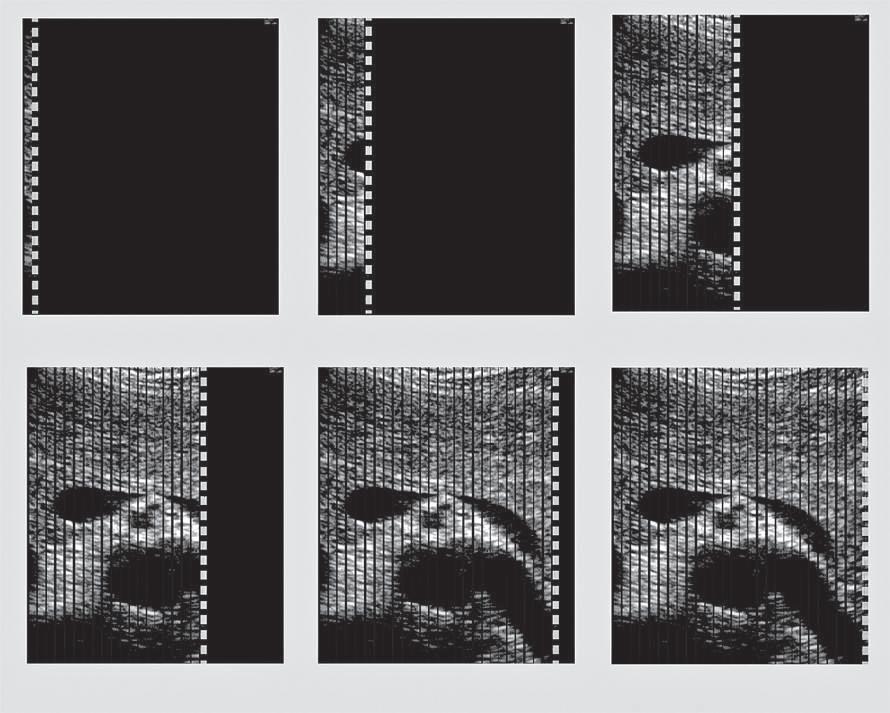

Three-Dimensional Ultrasound

Dedicated 3-D scanners used for fetal (Fig. 1.21), gynecologic, and cardiac scanning may employ hardware-based image registration, high-density 2-D arrays, or software registration of scan planes as a tissue volume is acquired. 3-D imaging permits volume

data to be viewed in multiple imaging planes and allows accurate measurement of lesion volume.

FIG. 1.21 Three-Dimensional Ultrasound Image, 24-Week Fetus. Three-dimensional ultrasound permits collection and review of data obtained from a volume of tissue in multiple imaging planes, as well as a rendering of surface features.